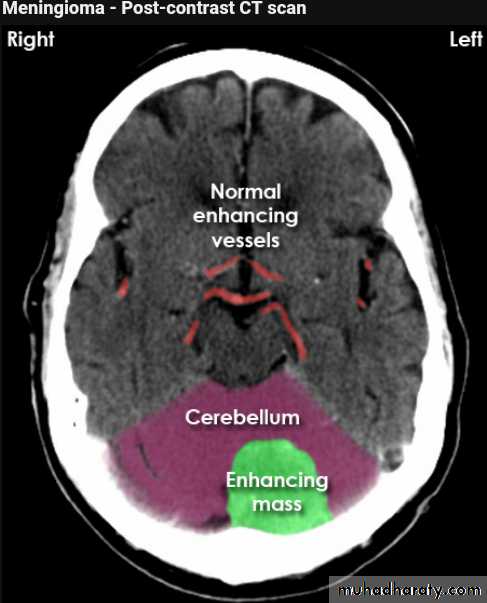

Meningioma

Benign tumor arise from the arachnid cells of the meningeal covering of the brain are most common primary intracranial neoplasm

Usually present in middle age female

it is well defined extra axial , located mainly at the convexity of the skull periphery

CT finding

meningioma presented as isodense area or slightly hyper density area with surrounded crescent of hypo density ( csf cap ) post contrast injection the lesion enhance homogeneously with enhancing Dural tail .

20 % show calcification

hyperostosis & thickening of the near by bony part of the skull & diplioc space .

it may be associated with little or no peri focal edema .

if the lesion associated with central necrosis with large perifocal edema meningio sarcoma should be excluded .